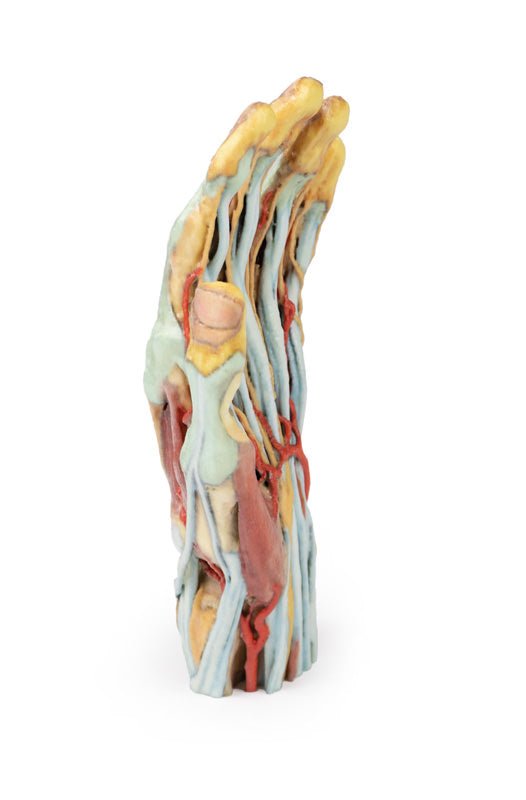

Tillverkade med den senaste 3D-utskriftstekniken och 100 % syntetiska material är 3D-dissektionsmodellerna en trogen kopia av den äkta varan, men utan den infektionsrisk som vanligtvis medför riktiga exemplar.

Våra 3D-dissektionsmodeller är utvecklade med tillstånd för användning av alla. Till skillnad från kadaver, som kräver omfattande användning och enorma resurser, både kemikalier och arbetskraft, för att skapa bara ett exemplar, kan våra modeller produceras säkert, användas av flera personer och förvaras var som helst.